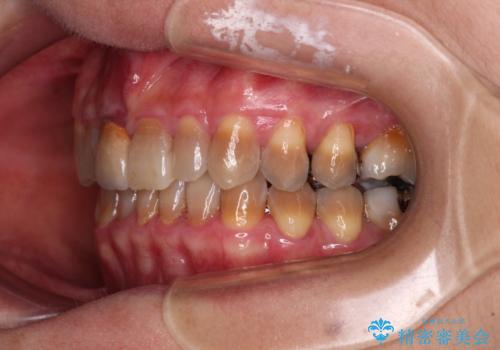

- 前歯のデコボコと、顎に負担のかかる歯並びを改善したいとのことで来院された患者様です。

うまく歯ぎしりができず、強く食いしばりをしてしまう咬み合わせであったため、奥歯に非常に負担がかかっていました。

インビザラインを用いて前歯のデコボコを改善するとともに、奥歯の咬み合わせを変えてスムーズに歯ぎしりできるように排列していくこととしました。

可能であれば上下正中を合わせ、左右の咬み合わせも改善したかったのですが、骨格的な左右差が大きかった上に、インビザラインでは限界があり、達成できませんでした。

それでも奥歯の負担を改善することができました。